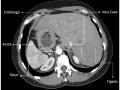

Tag: tomografia computadorizada

Diagnóstico por imagem em ginecologia - Quinto ano medicina

Seguimento por imagem dos principais cânceres ginecológicos